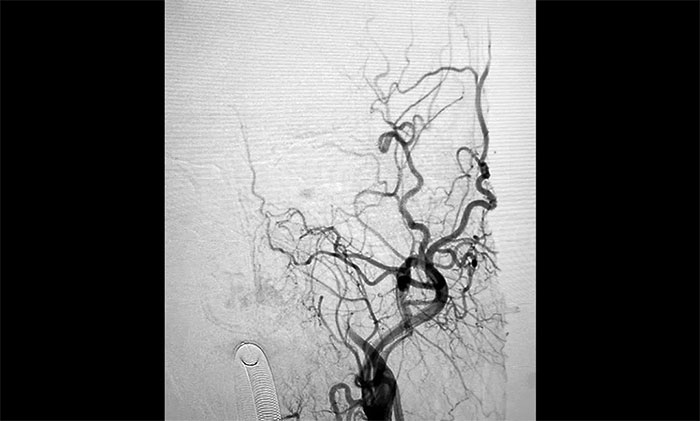

▲术前DSA影像:左侧颈内动脉眼动脉段以远闭塞

▲术后DSA影像:左侧颈内动脉血流恢复

术中脑血管造影可见:左侧颈内动脉眼动脉段以远闭塞……余血管未见明显异常。张琪博士在刘春、周林华、李喆医生协助下,通过右侧股动脉穿刺,将微导管、微导丝送达左侧大脑中动脉M1段,经多次抽吸+支架拉栓,顺利取出血栓。造影显示,颈内动脉眼动脉段血流恢复。

随后,微导丝超选至左侧大脑中动脉M1段远端,并以多枚球囊扩张残余重度狭窄处,造影提示狭窄较前明显改善,远端血流改善明显。最后顺利放入支架,造影提示支架贴壁良好,支架内血流通畅,远端血流良好,手术顺利完成。